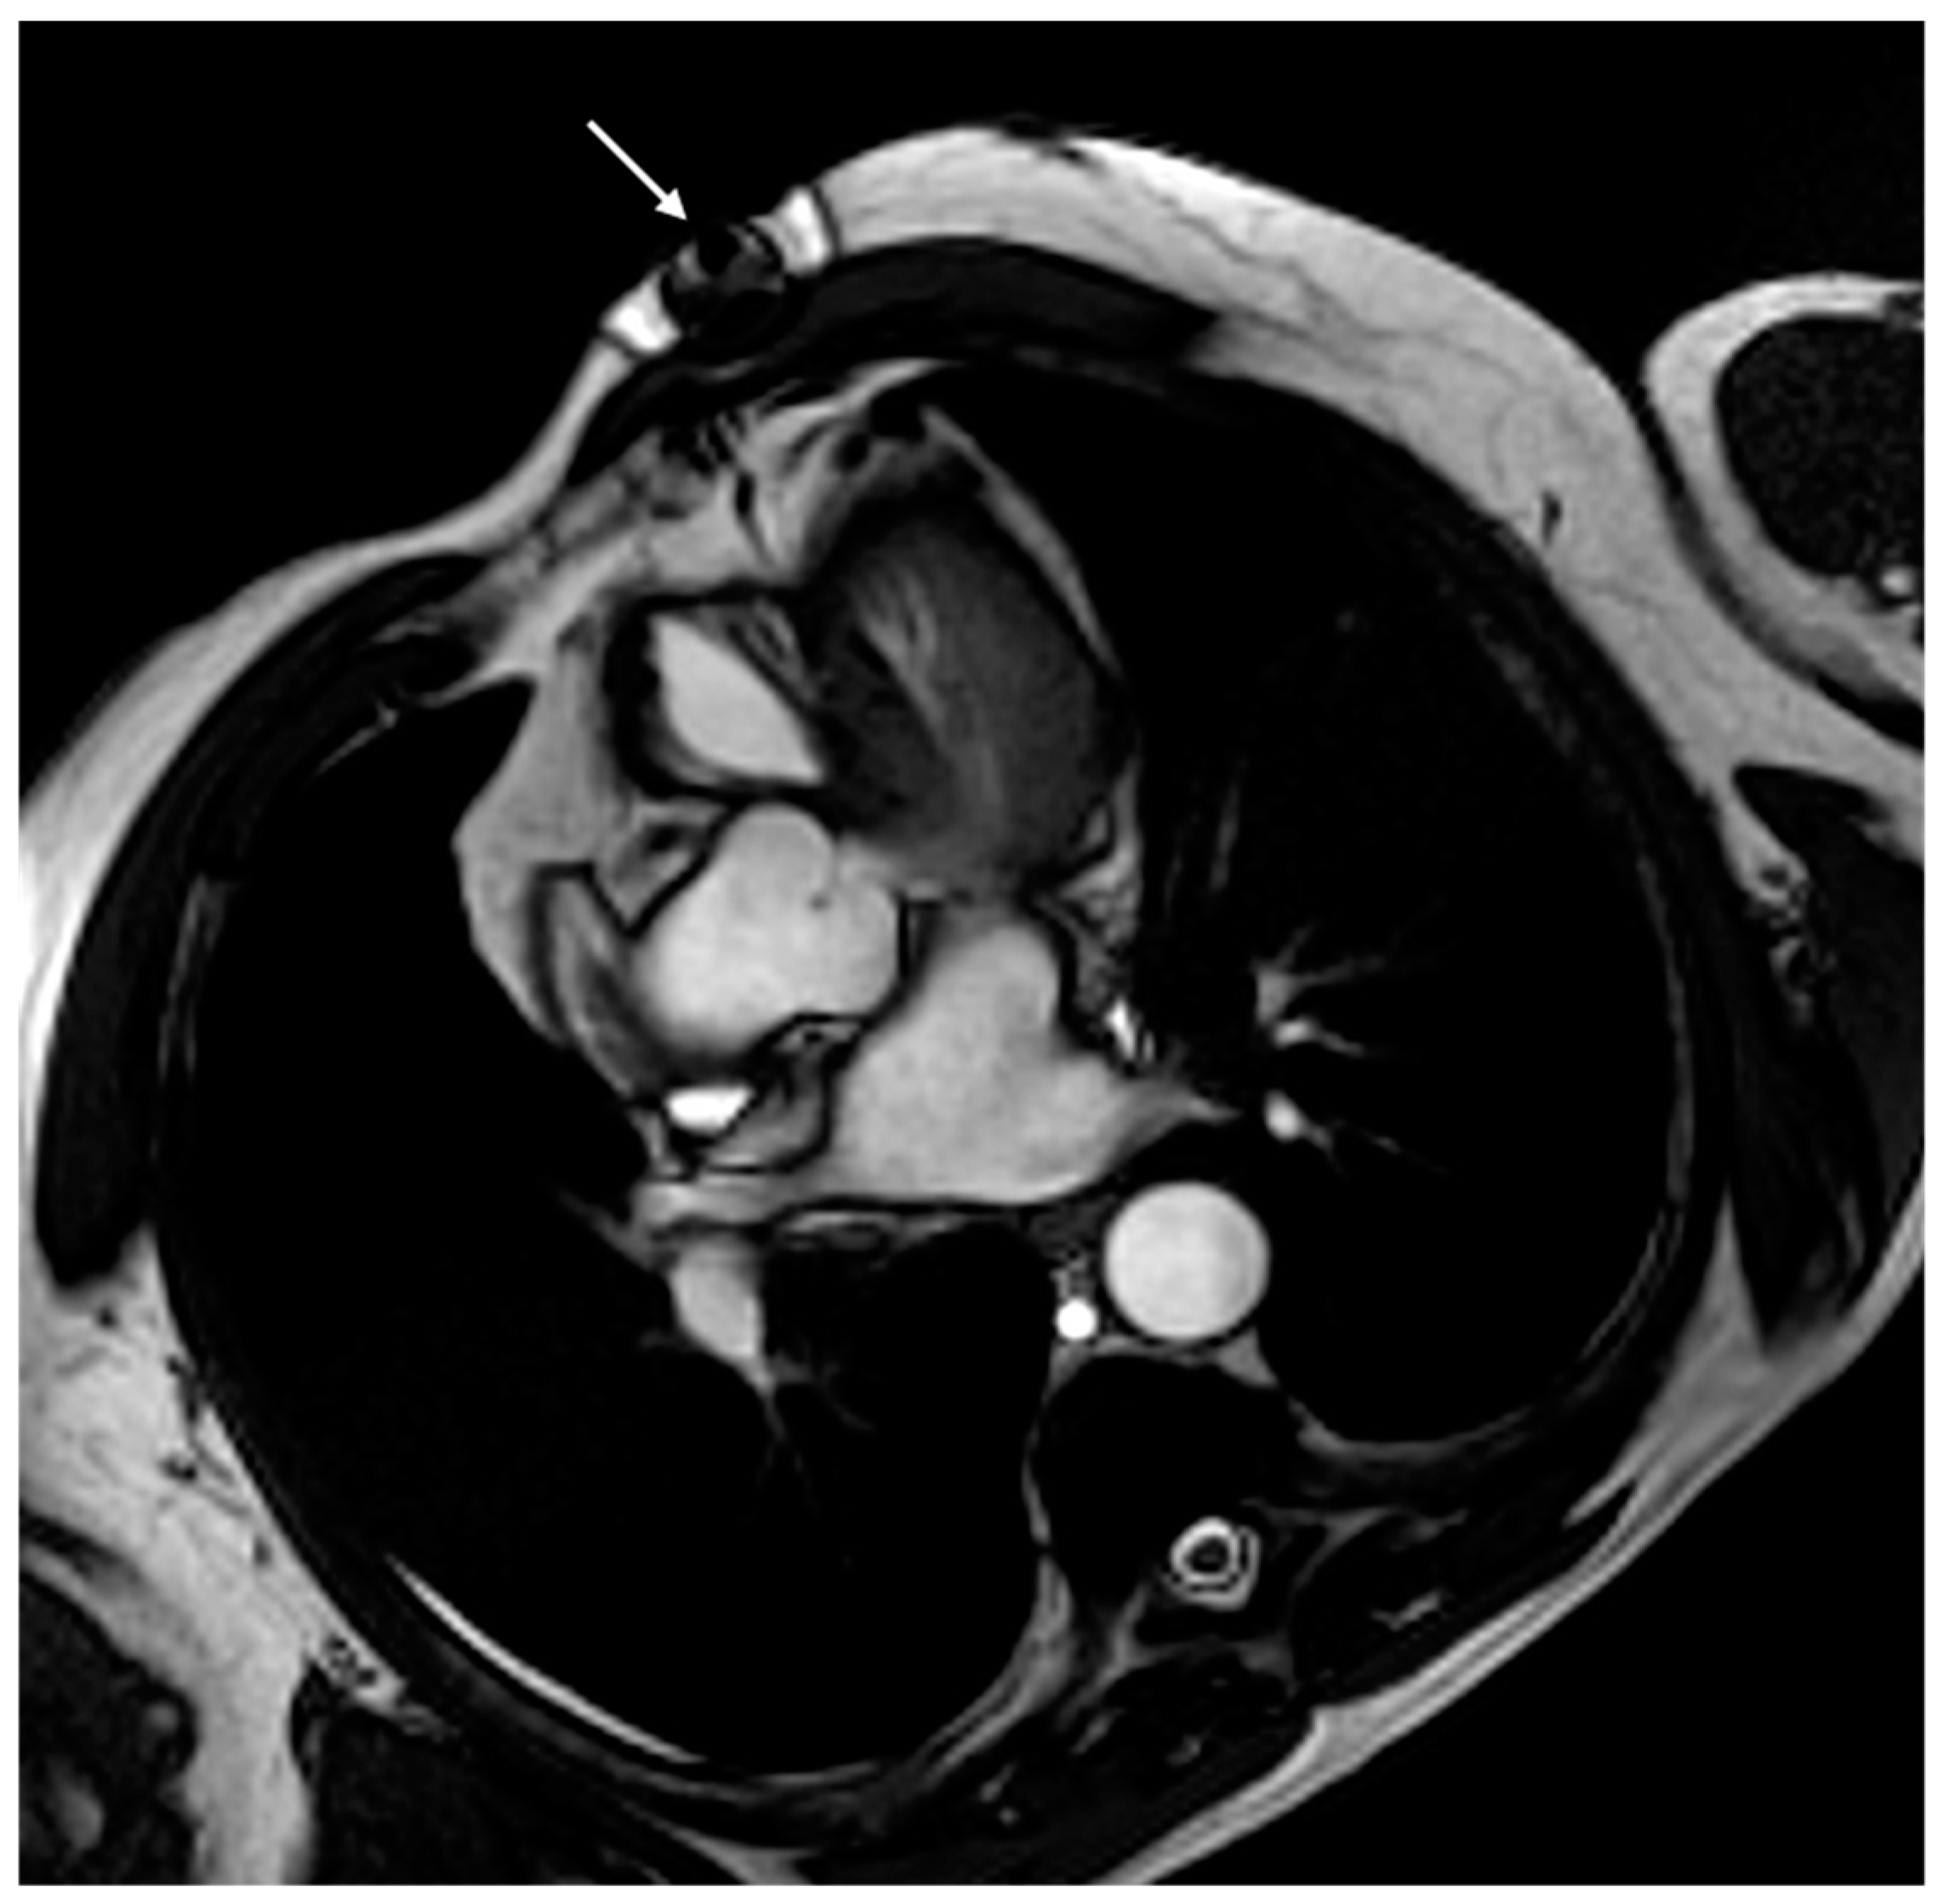

- Vuorinen, A.-M.; Lehmonen, L.; Karvonen, J.; Holmström, M.; Kivistö, S.; Kaasalainen, T. Reducing cardiac implantable electronic device–induced artefacts in cardiac magnetic resonance imaging. Eur. Radiol. 2022, 33, 1229–1242. [Google Scholar] [CrossRef] [PubMed]

- Runge, M.; Ibrahim, E.-S.H.; Bogun, F.; Attili, A.; Mahani, M.G.; Pang, Y.; Horwood, L.; Chenevert, T.L.; Stojanovska, J. Metal Artifact Reduction in Cardiovascular MRI for Accurate Myocardial Scar Assessment in Patients with Cardiac Implantable Electronic Devices. Am. J. Roentgenol. 2019, 213, 555–561. [Google Scholar] [CrossRef]

- Ibrahim, E.-S.H.; Runge, M.; Stojanovska, J.; Agarwal, P.; Ghadimi-Mahani, M.; Attili, A.; Chenevert, T.; Harder, C.D.; Bogun, F. Optimized cardiac magnetic resonance imaging inversion recovery sequence for metal artifact reduction and accurate myocardial scar assessment in patients with cardiac implantable electronic devices. World J. Radiol. 2018, 10, 100–107. [Google Scholar] [CrossRef]